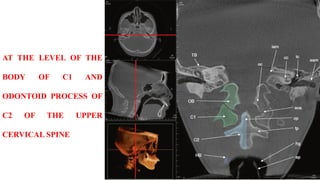

BODY OF C1 AND

ODONTOID PROCESS OF

C2 OF THE UPPER

CERVICAL SPINE

AT THE LEVELOF THE BODY OF C1 AND ODONTOID PROCESS OF C2 OF THE UPPER CERVICAL SPINE